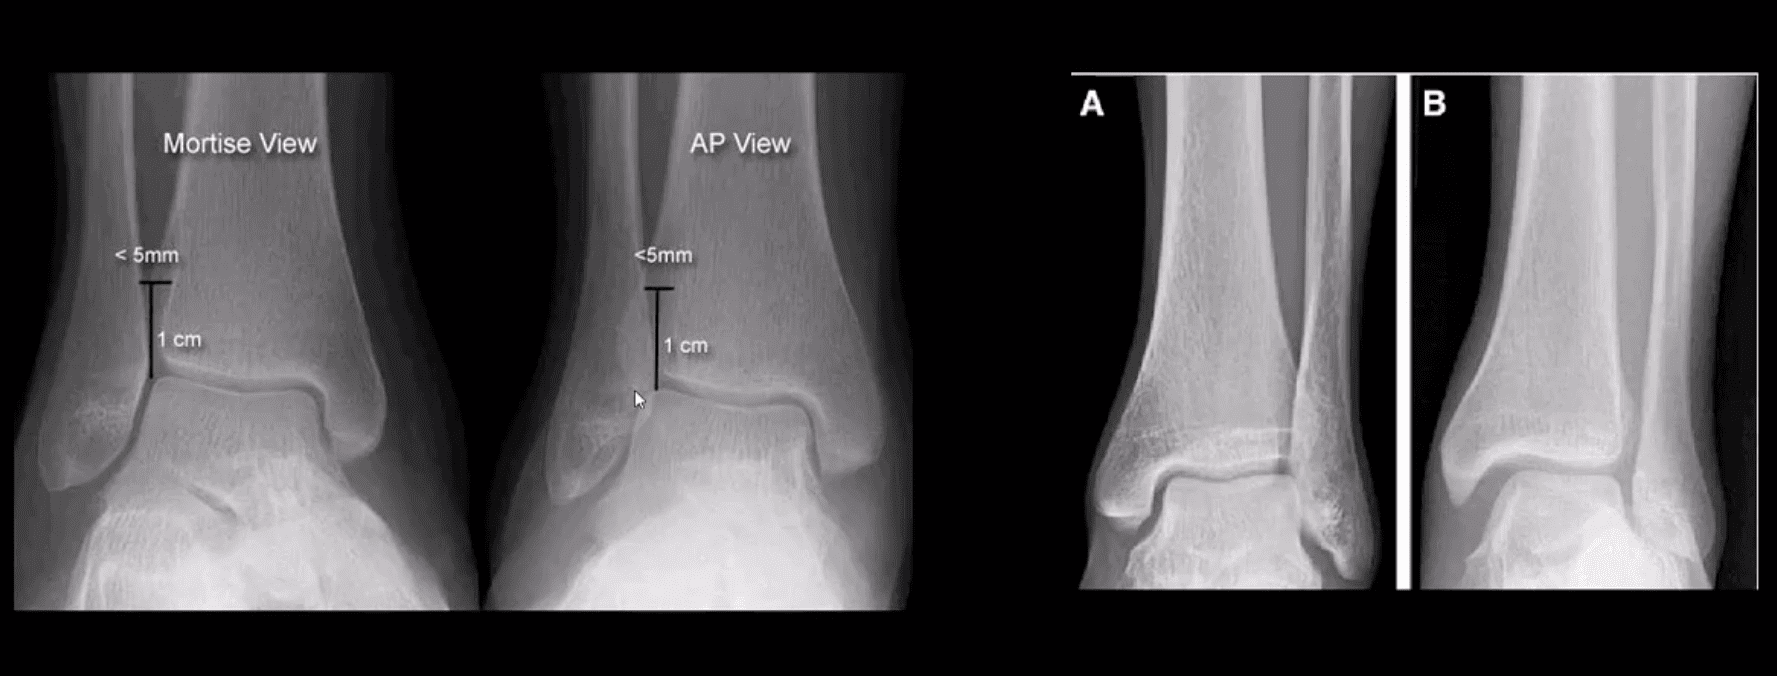

Mortise & AP Views

AP, Medial Oblique & Lateral Views

- Reveal infrasyndesmotic Fx of fibular malleolus (Weber A)

- Stable Injury

- Conservative care in the form of short-leg walking cast/boot can be used. Good recovery. If no evidence of ostechondral injury, relatively low chances of post-traumatic OA

- No further imaging required. MRI may help to reveal bone contusion and osteochondral injury

Weber B at Level of Syndesmosis

- Can be stable or unstable. On occasions, the decision is made during operative exploration.

- CT scanning may help with further evaluation

- Management: depends on stability. Additional stabilization required if syndesmosis is ruptured

Weber C

- AP, medial oblique and lateral views reveal Weber C – suprasyndesmotic injury with abnormal joint widening d/t disruption of tib-fib syndesmosis. Very unstable injury.